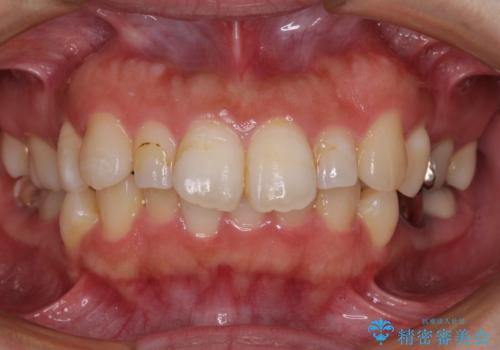

前歯と奥歯のガタガタを矯正で改善

担当医 河口智英